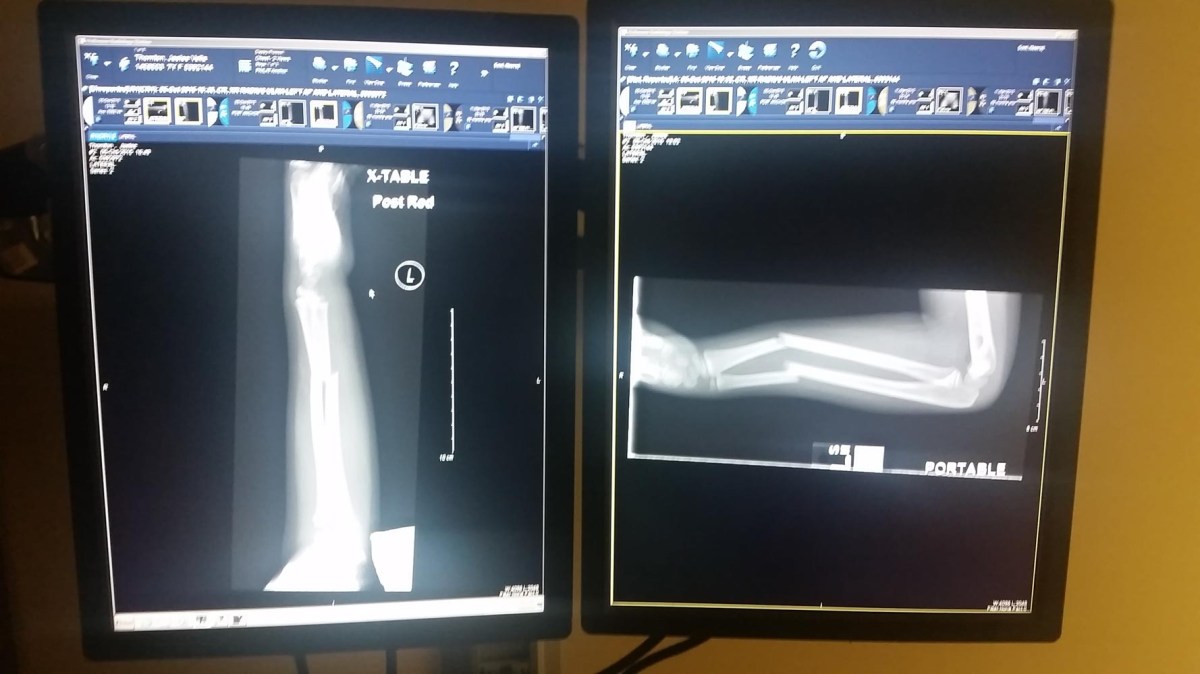

At the ER they put us back into a room right away. From there however it took forever. We ended up being their for 6 hours. She had multiple x-rays, they reset her arm and finally put a splint on it. It turns out she broke both bones in her arm and the doctor was concerned she may need surgery. We are still not sure if she’ll need surgery or not. The orthopedic doctor says it looks pretty good but we wont know for sure until she gets her cast off in 3 weeks. It has been quite an experience.